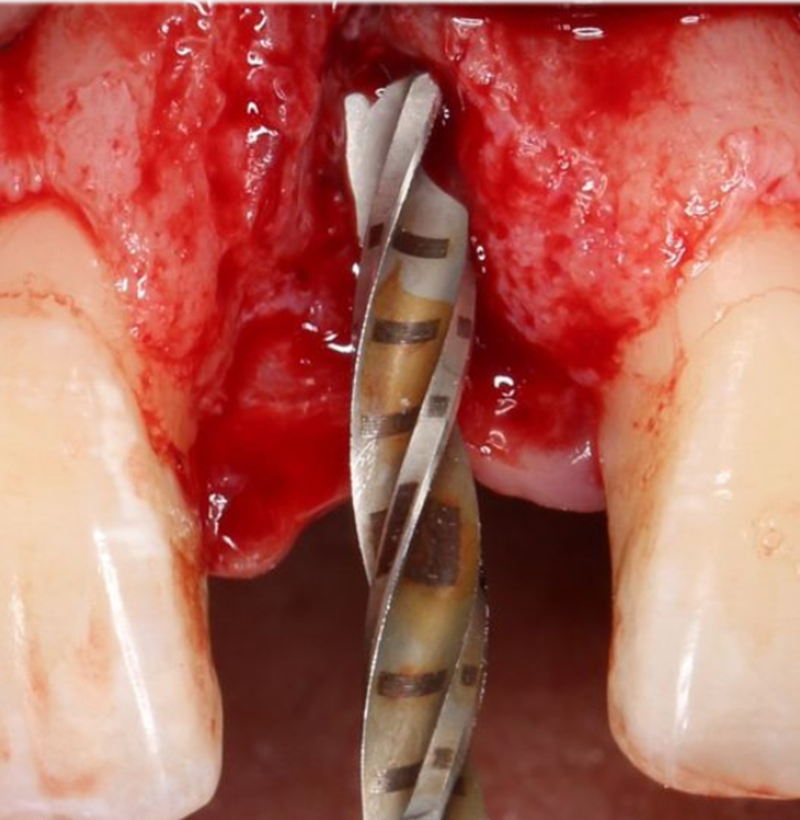

手術(shù)過程

定點

1.4mm小球鉆定點 △

2.3mm中號球鉆打開皮質(zhì)骨△

在易植美實時導(dǎo)航系統(tǒng)中,計算機引導(dǎo)球鉆精準按照術(shù)前設(shè)計定位△

2.2mm 先鋒鉆確定植入深度及軸向△

在實時導(dǎo)航系統(tǒng)中,實時引導(dǎo)先鋒鉆按照術(shù)前設(shè)計種植體軸向及深度進行擴孔△

2.8mm 擴孔鉆按種植體軸向擴大窩洞△

在實時導(dǎo)航系統(tǒng)中,實時引導(dǎo)擴孔鉆按照術(shù)前設(shè)計種植體軸向及深度進行擴孔△